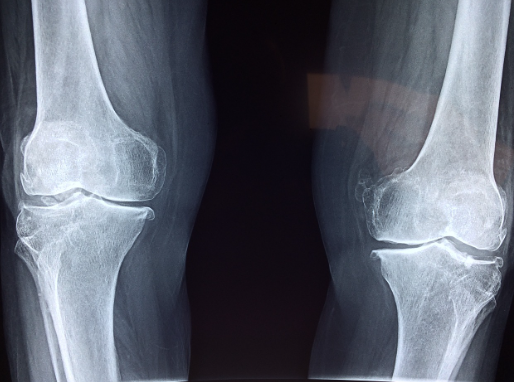

관절이란 무엇인지에 대하여 먼저 살펴보도록 하겠습니다. 관절이란 뼈와 뼈가 만나는 지점을 의미하며 활막, 인대, 힘줄, 근육 등의 구성 요소를 갖추고 있습니다. 인체나 동물의 뼈들은 서로 연결되어 있으며 이 연결 지점에서 움직임이 가능하게 하기 위해 관절이 형성됩니다. 관절은 뼈의 연결 부위를 부드럽게 움직일 수 있도록 도와주며 다양한 방향과 범위로 움직임을 제공합니다.

이 뼈들은 서로 대응되는 모양을 가지고 있으며 관절을 구성하는 부위에는 뼈를 연결해주는 연결 조직, 관절 주위를 둘러싸고 있는 관절 봉막, 뼈와 뼈 사이에서 마찰을 줄이는 연골 등이 포함됩니다. 관절은 다양한 형태와 기능을 가지고 있는데 각각의 관절은 특정한 움직임을 수행할 수 있도록 설계되어 있습니다. 일부 관절은 자유롭게 움직일 수 있는 볼과 소켓 형태로 되어 있고 다른 관절은 각각의 축 주위로 회전하는 형태를 가지고 있습니다. 인체에서도 다양한 유형의 관절이 존재합니다.

예를 들어 손목 관절, 팔꿈치 관절, 무릎 관절, 골반 관절 등이 있습니다. 이 관절들은 각각의 구조와 기능에 따라 다양한 움직임을 수행하며 운동과 일상 생활에서 중요한 역할을 합니다. 관절 내 연골은 지속적으로 마모되고 대체되며 이런 과정이 손상되면 관절염이 발생할 수 있습니다.

관절염은 여러 가지 원인으로 인해 관절에 염증이 생겨 통증과 기능 저하를 일으키는 상황입니다. 관절염의 종류는 다양하며 정확한 진단과 치료가 필요합니다. 관절 통증과 관절염은 다른 것이며 관절 통증이 있더라도 모든 경우가 관절염은 아닙니다. 관절염은 치료와 병의 경과가 다양하므로 정확한 진단과 치료가 중요합니다.